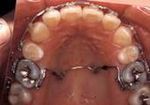

子供の矯正治療(第一期治療)

乳歯~永久歯の生え変わりの時期(~12歳頃まで)

FKO150.jpg

下あごの成長をうながす装置

主に取り外し可能な装置を用いて、生え始めた永久歯が適切な位置に生えるように促します。あごの成長の観察やコントロールもあわせて行います。治療期間は永久歯に生え変わるまでで、あごの大きさや、歯の大きさ、位置に問題がある場合は大人の矯正治療(第二期治療)へ移行します。